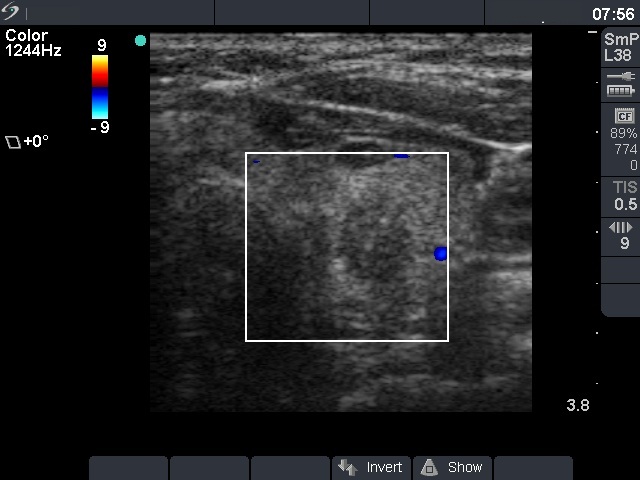

Ultrasonography: the thyroids were echonormal. There were two hypoechoegenic nodules next to each other in the left lobe. The upper had regular shape and presented a type 2 vascular pattern while the lower one had irregular borders, contained microcalcifications. The volume of the former nodule increased by 38% and the latter suspicious one by 72% over the previous 5 years.

Cytological diagnosis (from the irregular nodule): papillary cancer.

Histopathology: three distinct entities - a papillary microcarcinoma with a maximal diameter of 9 mm according to the nodule aspirated, an oxyphilic adenoma according to the other nodule and several hyperplastic nodules in both thyroids.